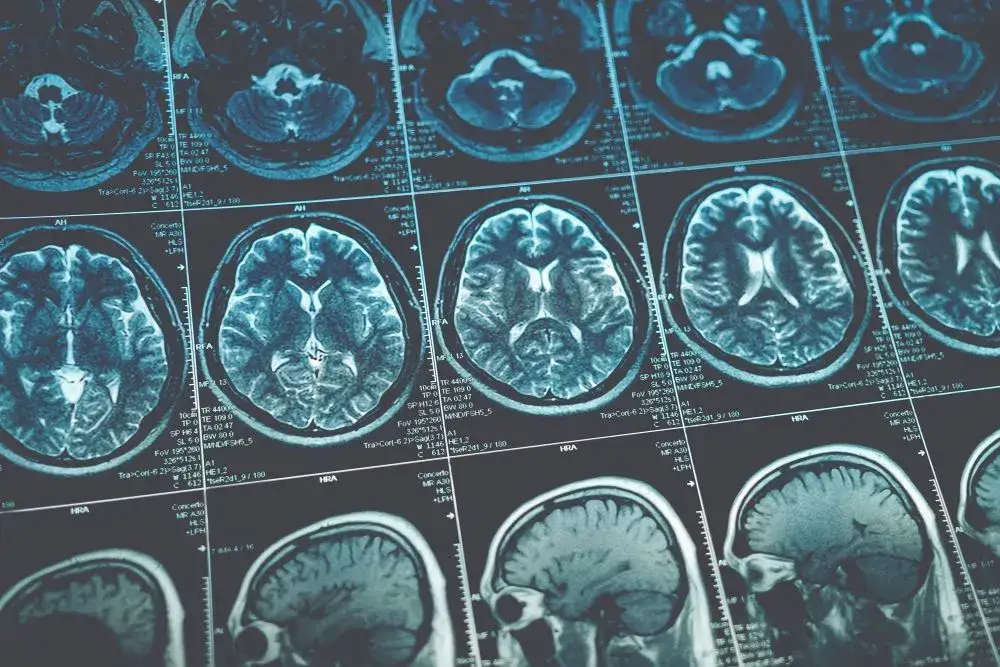

Aby zdiagnozować hiperostozę czołową, lekarze stosują różne metody diagnostyczne, które pomagają ocenić stan kości czołowej. Najczęściej wykorzystywane są zdjęcia rentgenowskie oraz tomografia komputerowa (CT). Te techniki obrazowania pozwalają na dokładne zobrazowanie struktury kości i wykrycie wszelkich nieprawidłowości. Dzięki tym badaniom możliwe jest zidentyfikowanie obszarów, w których występuje nadmierny wzrost kości, co jest kluczowe dla postawienia diagnozy. Właściwa ocena wyników badań jest niezbędna do dalszego postępowania medycznego.

Rola specjalistów w diagnozowaniu hiperostozy czołowej

Diagnostyka hiperostozy czołowej wymaga współpracy różnych specjalistów. Neurolodzy, radiolodzy oraz lekarze ogólni odgrywają kluczową rolę w procesie diagnostycznym. Neurologowie oceniają objawy neurologiczne, podczas gdy radiolodzy analizują wyniki badań obrazowych. Taka współpraca zapewnia kompleksowe podejście do diagnozy, co jest niezbędne dla ustalenia właściwego planu leczenia. Dzięki temu pacjenci mogą otrzymać odpowiednią pomoc w odpowiednim czasie.